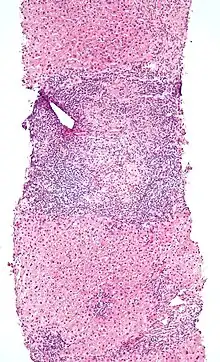

Micrograph of PBC showing bile duct inflammation and injury.

On microscopic examination of liver biopsy specimens, PBC is characterized by chronic, non-suppurative inflammation, which surrounds and destroys interlobular and septal bile ducts. These histopathologic findings in primary biliary cholangitis include the following:[34]

- Inflammation of the bile ducts, characterized by intraepithelial lymphocytes, and

- Periductal epithelioid granulomata.

- Proliferation of bile ductules

- Fibrosis (scarring)